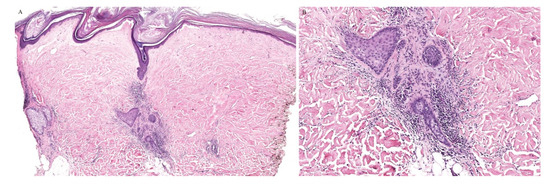

A clinically folliculocentric variant of lichen sclerosus has only been reported twice before in the literature. These cases had extragenital presentations of typical LSA lesions distributed in a perifollicular pattern. In both cases, histopathologic examination did not reveal a follicular infiltrate [23,24]. Nonetheless, an inflammatory infiltrate around the hair follicle can be observed in histopathologic specimens of lichen sclerosus, even in the absence of follicular involvement clinically (Figure 4).

Figure 4. (A,B) Lichen sclerosus with perifollicular inflammation.